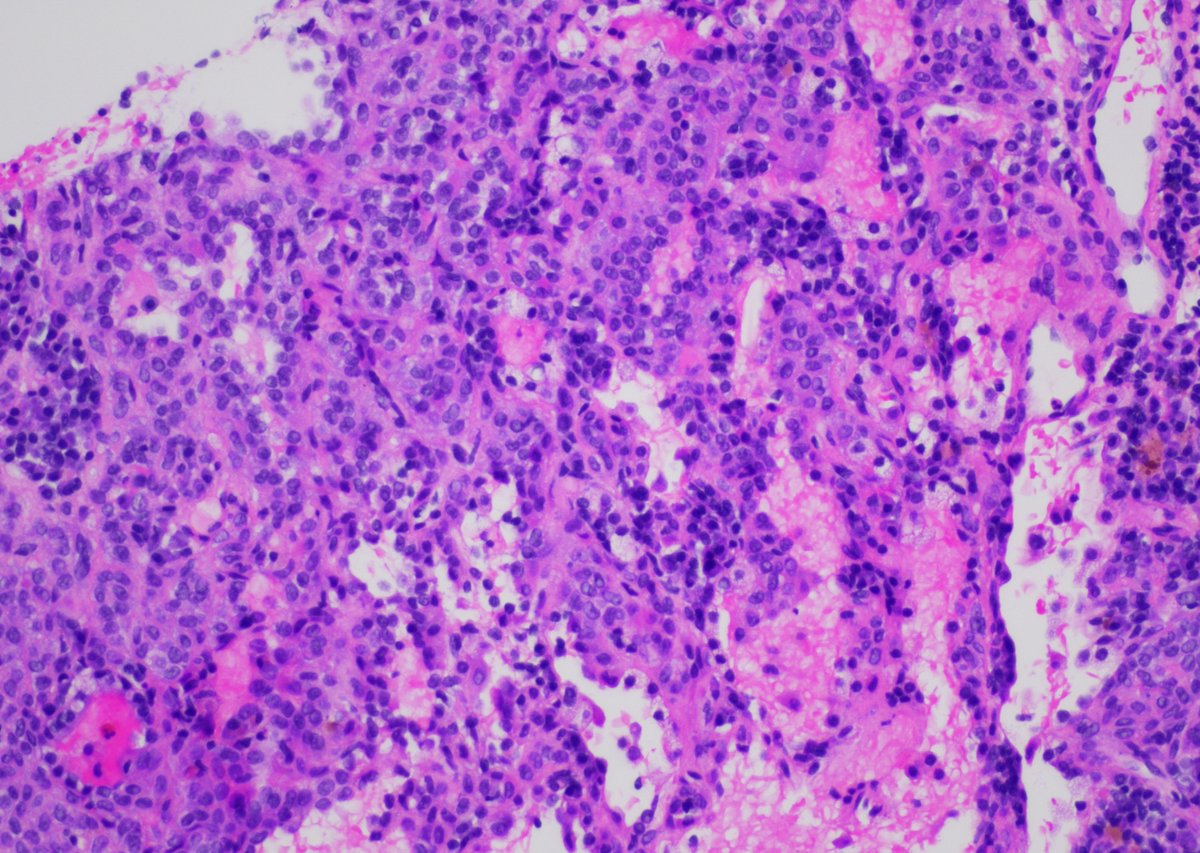

65yo F with 1.3cm LLL lung nodule. Core biopsy of the mass was performed. #pathology #pathtwitter #pulmpath #pathboards Jui Choudhuri Ridin Balakrishnan, MD Pembe Oltulu, MD Celina Stayerman MD Vish Killari MD MPH Brian Cox, MD, MAS Rana Saleh, MD Adam L. Booth, MD